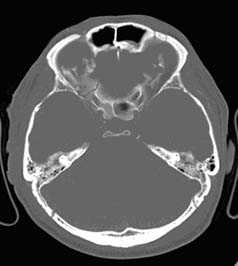

Применение компьютерной томографии в нейротравматологии существенно изменило представление о возможностях диагностики различных черепно-мозговых повреждений. КТ является в настоящий момент «золотым стандартом» - наиболее информативным методом обследования больных с черепно-мозговыми травмами и позволяет в самые короткие сроки судить о механизмах возникновения поражения мозга, его характере, распространенности, выраженности отека и дислокации мозга, а также динамике этих изменений.

КТ позволяет последовательно изучить мягкие ткани головы, кости черепа, вещество мозга, эпидуральные, субдуральные, субарахноидальные пространства, цистерны основания и желудочки мозга:

- выявить переломы свода и основания черепа (с чувствительностью, намного превышающей традиционную рентгенографию) ,

Визуализация минимальных количеств излившейся свежей крови, уверенная дифференциация ее от других внеклеточных жидкостей, слежение за динамикой отека и набухания головного мозга, некроза и восстановления его структур с одновременным распознаванием переломов костей черепа, особенно его основания, составляют преимущества КТ перед магнитно-резонансной томографией.